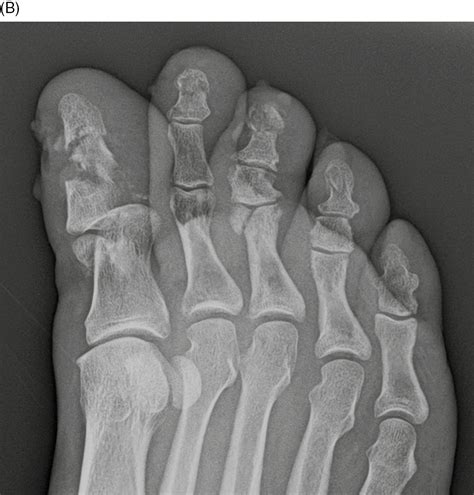

Your doctor will likely order an X-ray to determine the severity and location of the break. Treatment options will vary based on the findings:

• Surgery: In rare cases where the bone is severely displaced or fragmented, or if the break involves the joint surface, surgical intervention with pins or screws may be necessary to realign the bone.